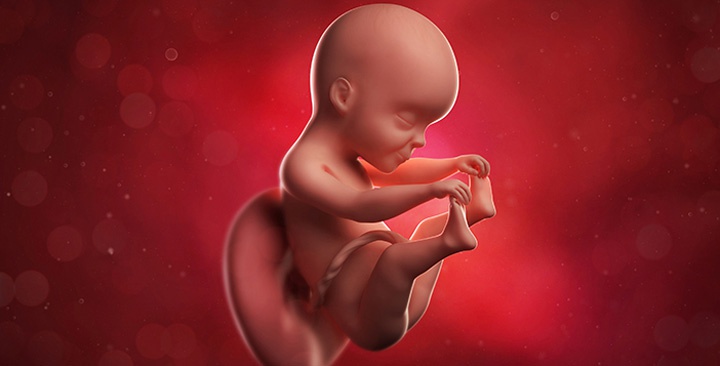

Как выглядит ребенок

Кожа малыша расправляется, становится менее морщинистой и светлеет. Подкожно-жировая клетчатка увеличивается. Лицо плода уже похоже на лицо новорожденного: выражен нос, сформированы веки, ресницы и брови, щечки округляются, ушные раковины занимают свое место и увеличиваются.

Большинство малышей уже лежат головкой вниз, но если он находится ягодичками вниз, время на переворот еще есть. Из-за уменьшения пространства движения становятся более ощутимыми.

Ваш малыш по размерам как помело, вес около 800 грамм, длина 320 мм (новорожденный имеет рост около 50 см), сердцебиение 120–160 уд./мин.